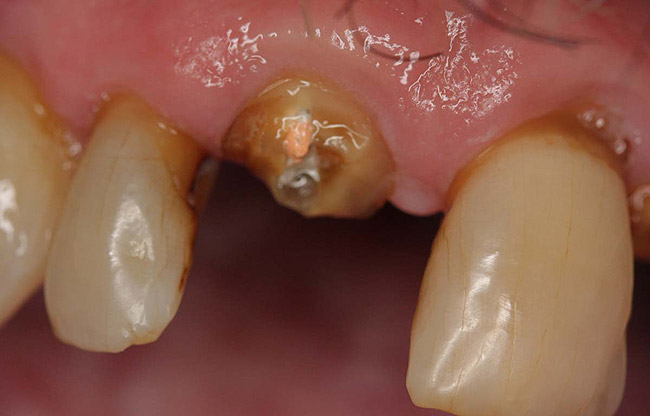

A Class IN maxillary bicuspid was previously restored with a fiber post and an all-porcelain crown (Figure 1). The forces of the oral environment resulted in fracture of the fiber post and crown failure. The remaining fiber post in the root was removed, and anti-rotational areas were prepared for a cast post (Figure 2). A gold cast post was constructed at a dental laboratory, using an indirect technique (Figure 3). A porcelain-fused-to-metal (PFM) crown was constructed with a bevel finish to provide a ferrule and reduce forces on the post (Figure 4 and Figure 5).

Figure 2  Same second bicuspid as Figure 1 after removal of the fractured fiber post.

Figure 2